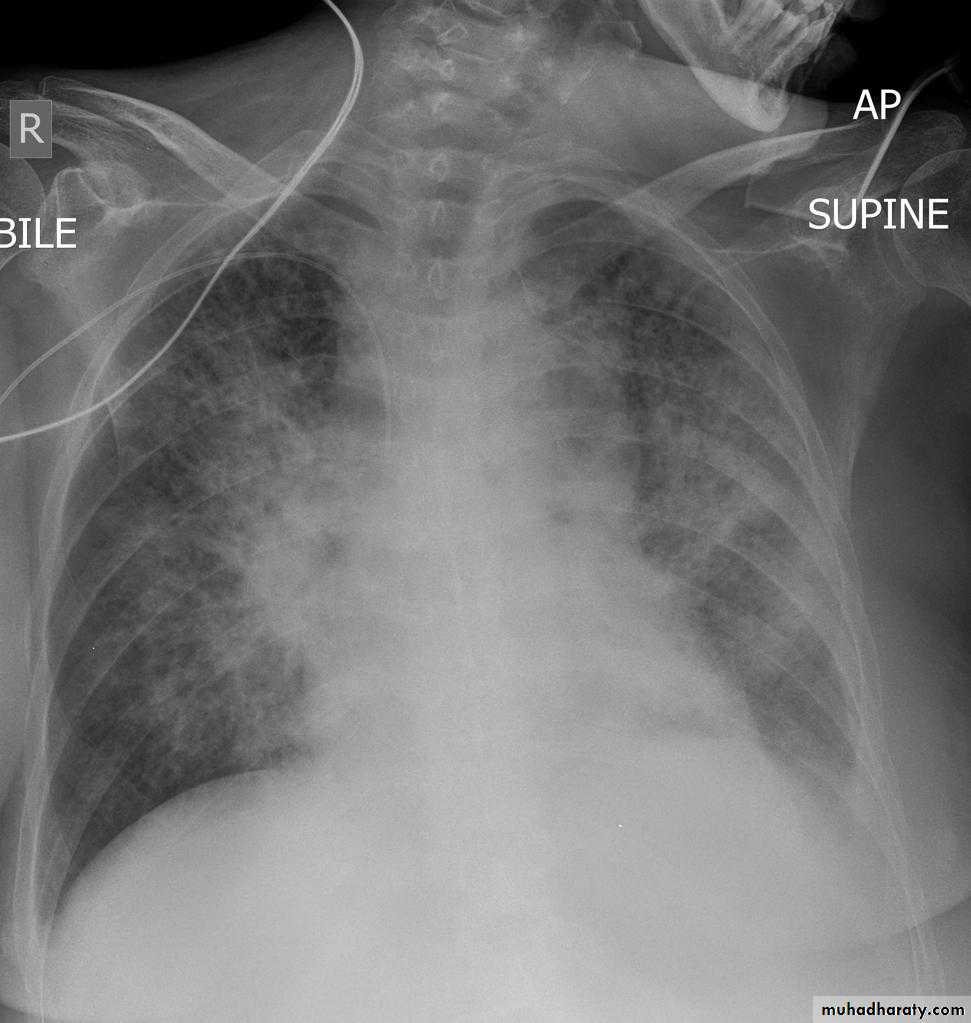

Pulmonary edema is a broad descriptive term and is usually defined as an abnormal accumulation of fluid in the extra-vascular compartments of the lung .

radiograph include if pressure > 25 mmHg the findings of :

1.cardiac size/cardio-thoracic ratio: useful for assessing for an underlying cardiogenic cause or association2.Pulmonary Alveolar edema: bat wing pulmonary opacities

3.Pulmonary interstitial edema: presence of peri-bronchial cuffing///septal lines: Kerley lines become more prominent4.pleural effusions

5.Central pulmonary venous engorgement

6.pulmonary blood flow distribution& upper lobe pulmonary venous diversion

Alveolar pulmonary edema